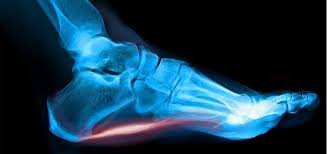

족저근막염, 아킬레스건염 - 가장 확실한 치료 방법 !!!

족저근막염이나 아킬레스건염으로 고생 중이신가요? 특히 아침에 일어나 첫 발을 디딜 때, 또는 오랜 시간 앉아 있다가 다시 걸을 때 발뒤꿈치가 찌릿하게 아프다면 족저근막염이나 아킬레스건염일 가능성이 높습니다. 이 글에서는 이 질환을 빠르게 낫게 할 수 있는 매우 쉬운 방법을 알려드립니다. 족저근막염과 아킬레스건염의 공통점두 질환 모두 반복적인 손상으로 인해 발생합니다. 족저근막과 아킬레스건은 한 번 손상되면 인체의 치유반응으로 자연치유하려고 노력하지만, 우리가 다시 걷거나 움직이면서 계속 손상을 주기 때문에 낫지 못하는 것이죠. 겨울에 입술이 트고 찢어졌을 때를 떠올려보세요. 겨울철 건조한 날씨에 입술이 말라 있을 때 하품을 하면 찢어지기 쉽습니다. 찢어진 입술이 낫기 전에 하품을 하거나 식사 중 입..